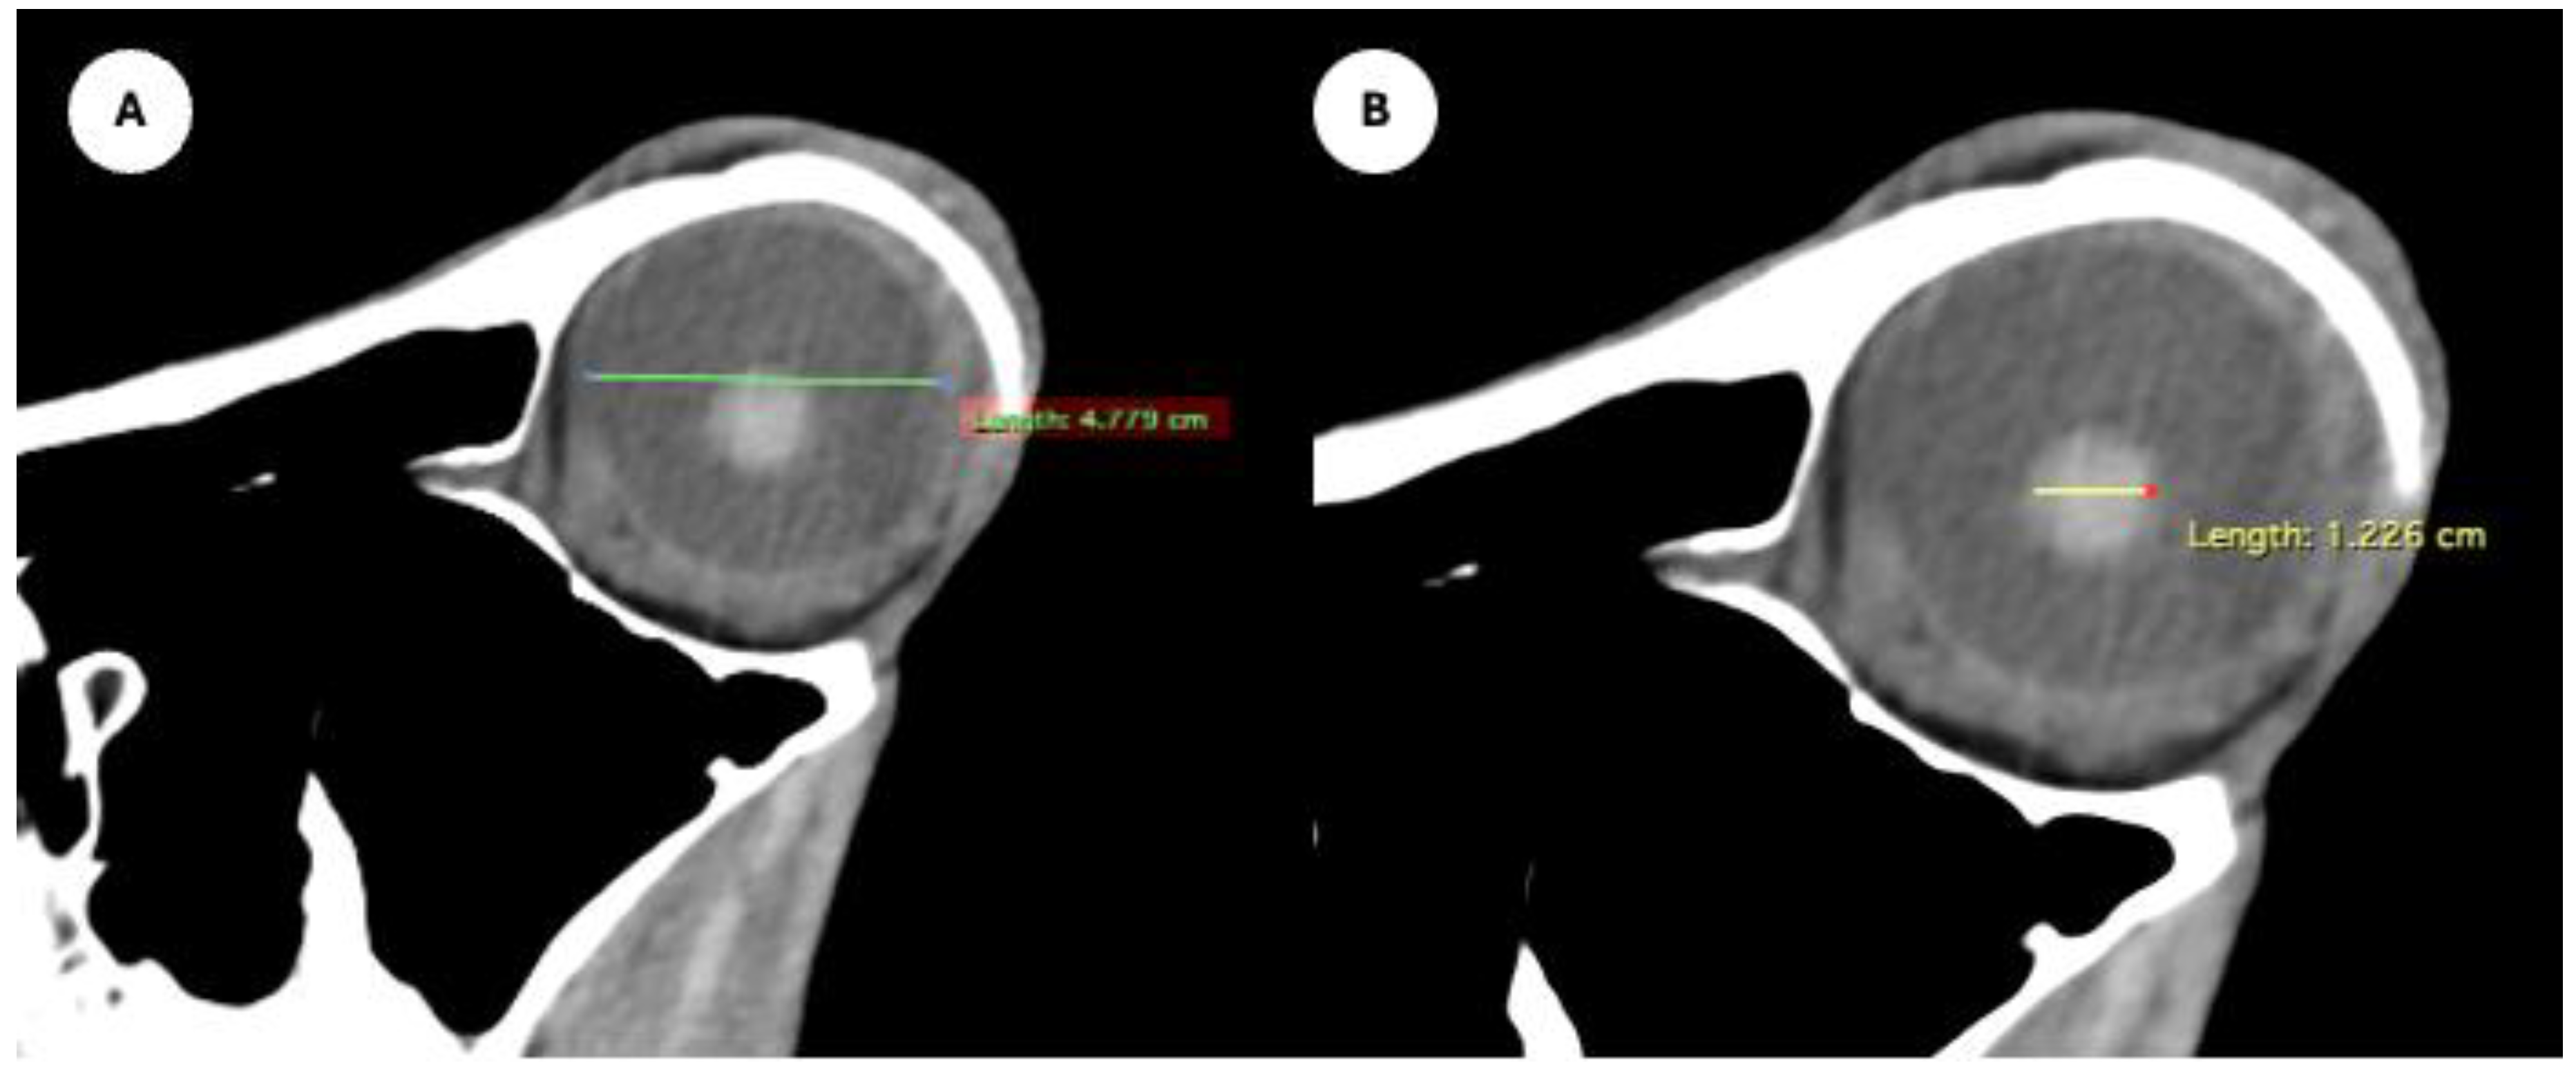

- Eyeball rostrocaudal length: Maximal anteroposterior distance of the eyeball from the internal surface of the cornea to the internal surface of the choroid/retina/sclera (Figure 4A).

- Lens rostrocaudal length: Maximum anteroposterior distance of the lens measured along its midline (Figure 4B).